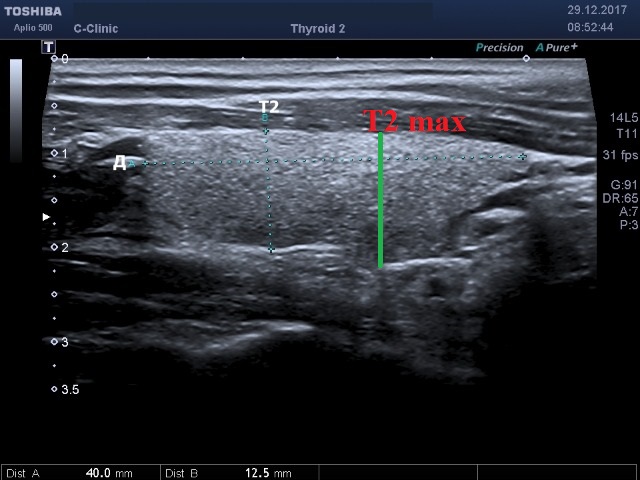

Моё измерение толщины Т-2 в данном случае является максимальным в срезе, на сайте снимок меньшего размера (разрешения), чем исходник на мониторе сканера, поэтому нижний (задний) контур кажется ниже, как Вы и измерили, а на самом деле не так.

Эдуард, я думаю смысл понятен! Не спорю, вам виднее было где ставить калиперы, чтобы вывести максимальный размер.Олег, Вы измеряете толщину доли там, где и длину, беря при этом максимальный передне-задний размер. Понятно.